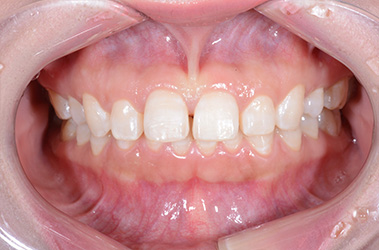

治療後

治療前